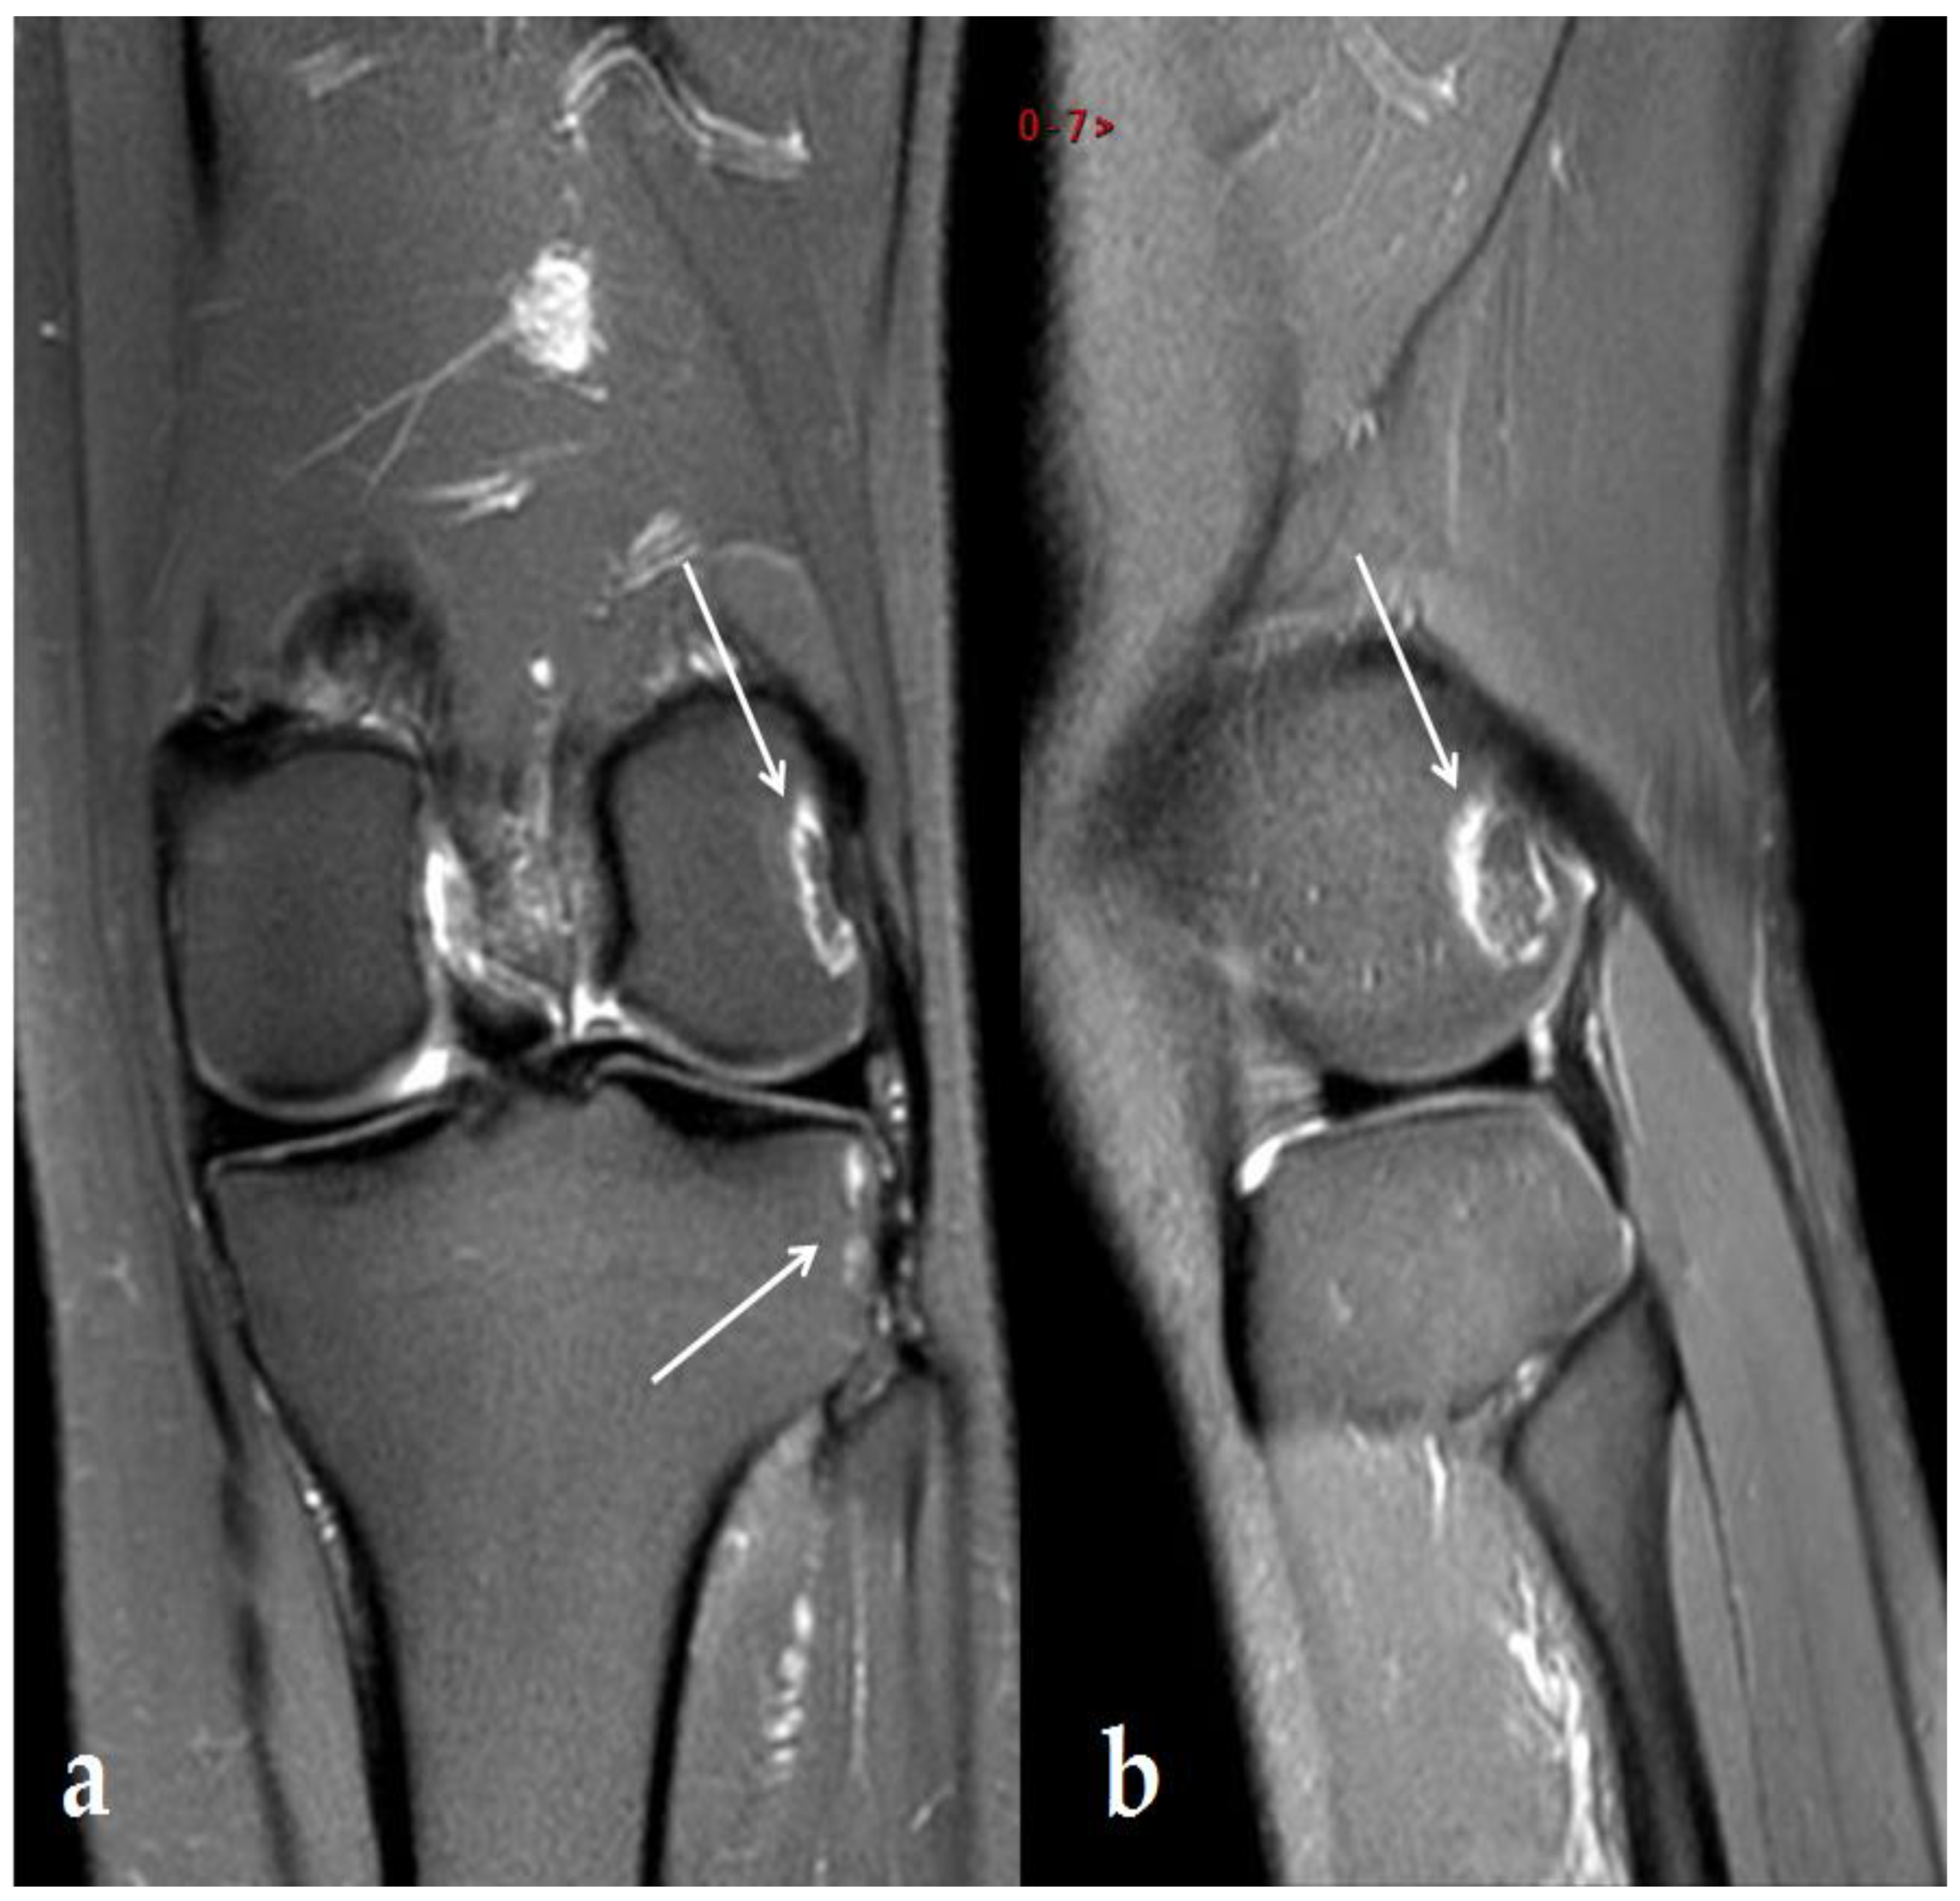

- Yeh, L.-R.; Chen, C.K.H.; Tsai, M.-Y.; Teng, H.-C.; Lin, K.-L. Focal Bone Abnormality as a Complication of Ultrasound Diathermy: A Report of Eight Cases. Radiology 2011, 260, 192–198. [Google Scholar] [CrossRef]

- Kim, S.J.J.; Kang, Y.; Kim, D.H.; Lim, J.Y.; Park, J.H.; Oh, J.H. Focal Bone Marrow Lesions: A Complication of Ultrasound Diathermy. Clin. Shoulder Elb. 2019, 22, 40–45. [Google Scholar] [CrossRef]